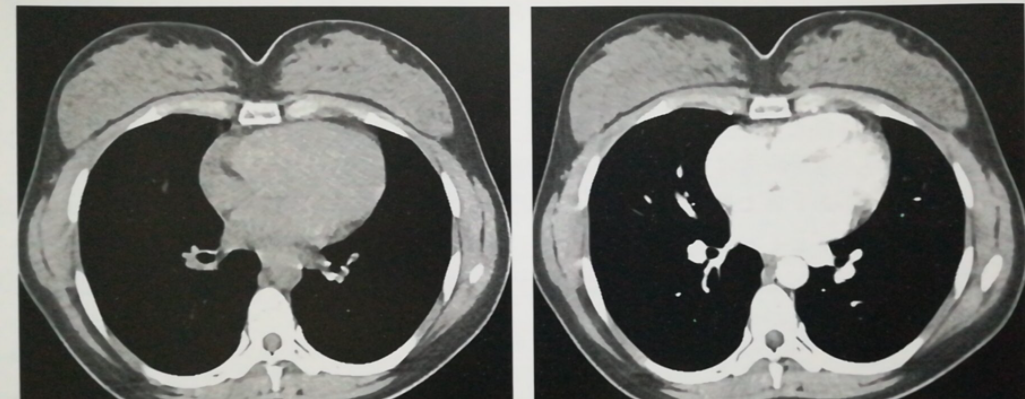

循环系统。CT检查主要应用于心包疾病、主动脉瘤等大血管病变、冠状动脉病变、心肌病变等,其中大家最常接触的就是冠状动脉内支架中的运用。

当然还有女性乳房,CT检查与乳房钼靶X线摄影特别像,但比这又有更高的空间分辨率和软组织分辨率,不但可以显示乳房腺体或乳房内病变的细节,同时对病变组织收尾结构和远隔器官的受累情况也有一个很详细的评估。

(如图为一位20岁女性致密型乳房)